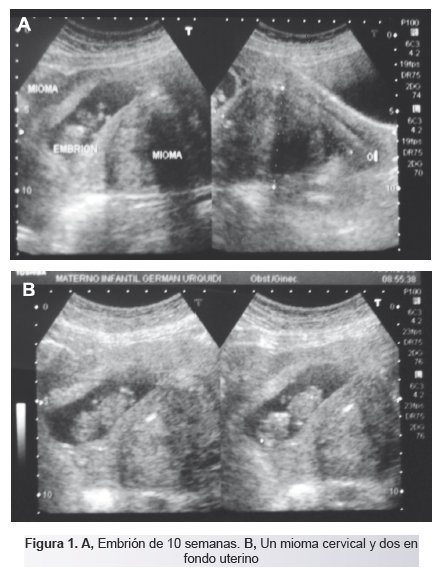

Gran Mioma Uterino Y Embarazo Reporte De Un Caso

Pdf Gran Mioma Uterino Y Embarazo Reporte De Un Caso